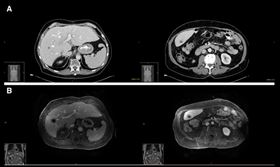

肝硬化換肝竟變肝癌末期 醫師揭恐怖真相

死亡後器官捐贈可以幫助他人延續生命,但也可能發生不如...